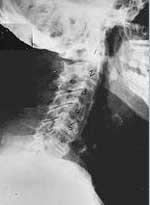

This is a side x-ray view of the neck. As with all the pictures you will see on this page, the patient is looking to the right of the screen, so you are viewing the right side of their neck. We will call this picture a "near normal" spine. Compare this spine with the ones you will see below on this page. Notice the normal forward curve of the neck. This curve helps absorb shock. Notice how each of the disc spaces between C2 (second bone in neck) and C7 are thick and even, this again is normal. Also notice how the front portions (right on the x-ray) of each of the vertebrae (called the 'body' of the vertebrae) are fairly square with clear and well defined borders. This type of arrangement is normal in the neck. Normal vertebrae in other parts of the spine also have similar characteristics to what we see here. When subluxations occur and are left uncorrected, ongoing relentless changes occur that result in damage to the structure and function of the spine along with nerve damage and the resulting problems caused from improper nerve supply.